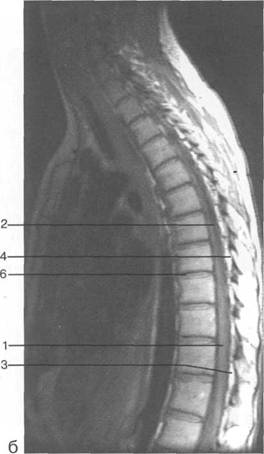

К моменту рождения (рис. 3.1) тело позвонка почти полностью состоит из к 141s183b 86;стной ткани, за исключением лимбусов, которые остаются хрящевыми. Дуга представлена двумя половинами, не слившимися ни с телом позвонка, ни между собой. Суставные отростки сохраняют перифе

MPT. Cw_v.